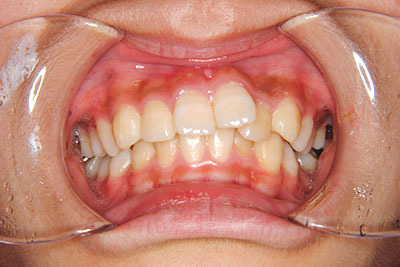

小学生高学年や中高生で矯正治療を考えている方へ

歯が乳歯から永久歯に生え変わった小学生高学年や、中高生でも矯正治療に手遅れということは全くありません。

成長中の顎の骨を矯正できたり、この時期の矯正はおとなになってから矯正治療を始めるよりも短期間で済むことがほとんどです。当院だとおおよそ1年で動的治療(マルチブラケット装置をつける期間)が終わることが多いです。